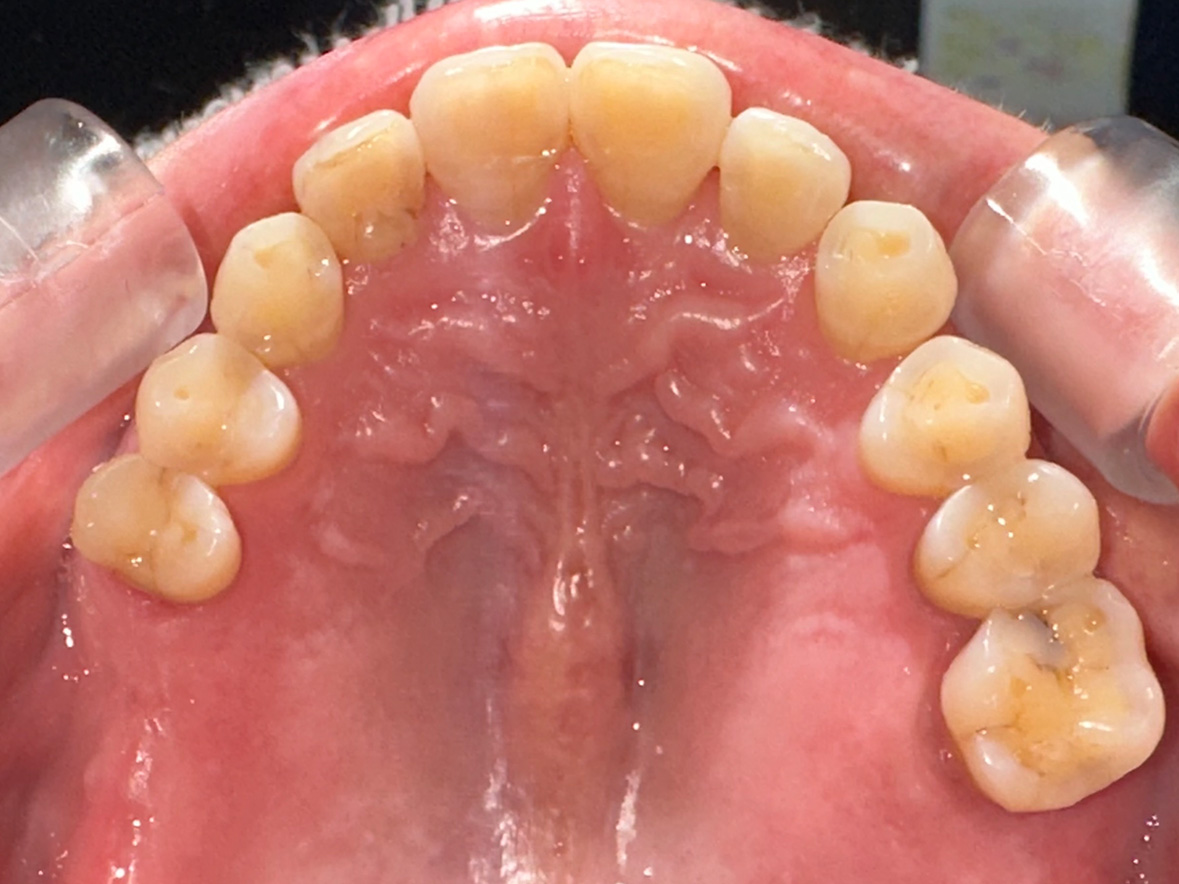

症例3

患者様の年齢 60代男性 主訴 歯が痛い 治療内容 左下456インプラント治療

抜歯即時インプラント埋入後3ヶ月の待機期間後、ジルコニアによる上部構造装着費用 77万円 治療期間・通院回数 4ヶ月/5回 デメリット・リスク 外科処置に伴う痛み・腫れ・出血・合併症の可能性があります。 -